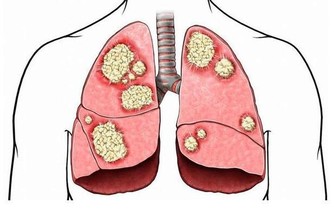

生活需要偶爾抑制排便、憋便是在所難免的,但如果經常或長時間抑制排便,可使直腸對糞便刺激的反應降低或消失。糞便在大腸內停留過久,水被吸收過多而使其乾燥,容易引起排便困難,產生便秘和痔瘡,極端嚴重的還會引起腸道的相關疾病。